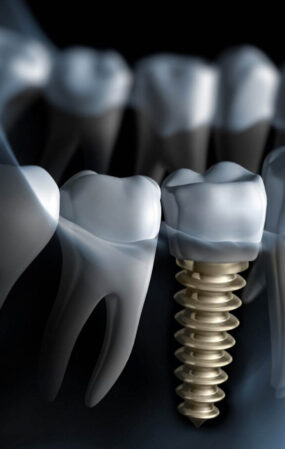

Tedavi

Dişinizdeki vakanın tedavisini uyguluyoruz.